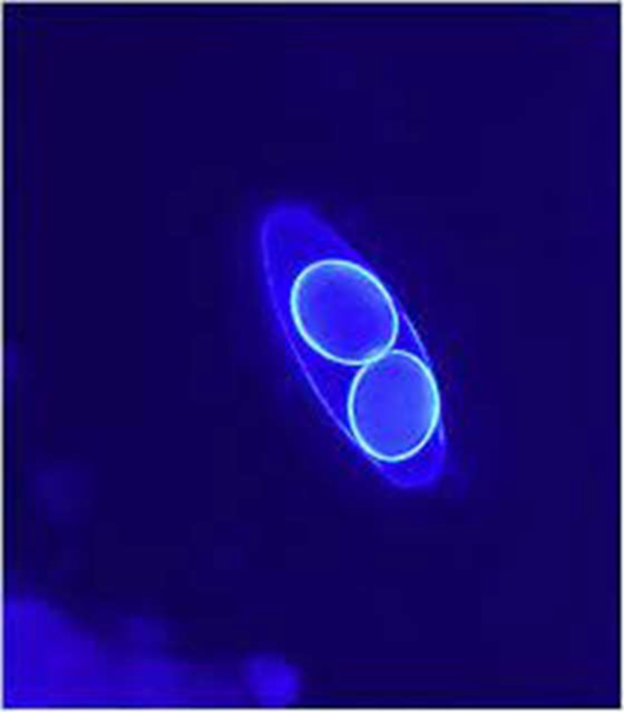

Cystoisospora

Calcofluor White Stain